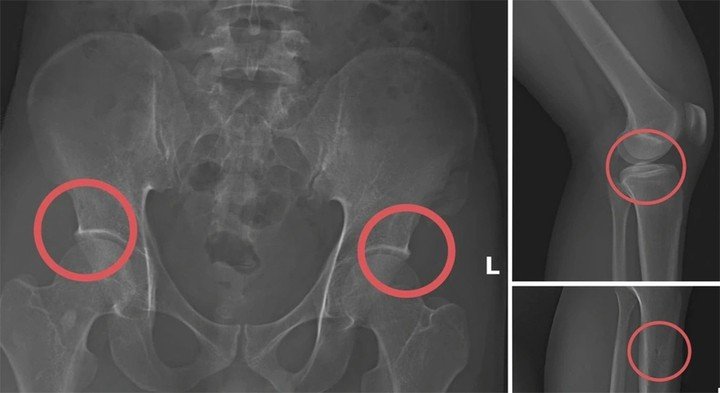

Kịch bản kinh hoàng được tái hiện tại buổi thực nghiệm cho thấy, sau khi tiêm thuốc gây mê cho đồng phạm, Châu đã trực tiếp dùng búa đinh đập nát các vùng xương chậu và xương đùi của nạn nhân để tạo ra những tổn thương thực thể nghiêm trọng. Khi tỉnh dậy với những vết thương thật, các đối tượng tiếp tục dàn dựng hiện trường giả như bị điện giật hoặc trượt ngã khi đi suối để hợp thức hóa hồ sơ bệnh án tại các cơ sở y tế.

Hình ảnh cho thấy các đối tượng tự gây thương tích nhằm trục lợi.